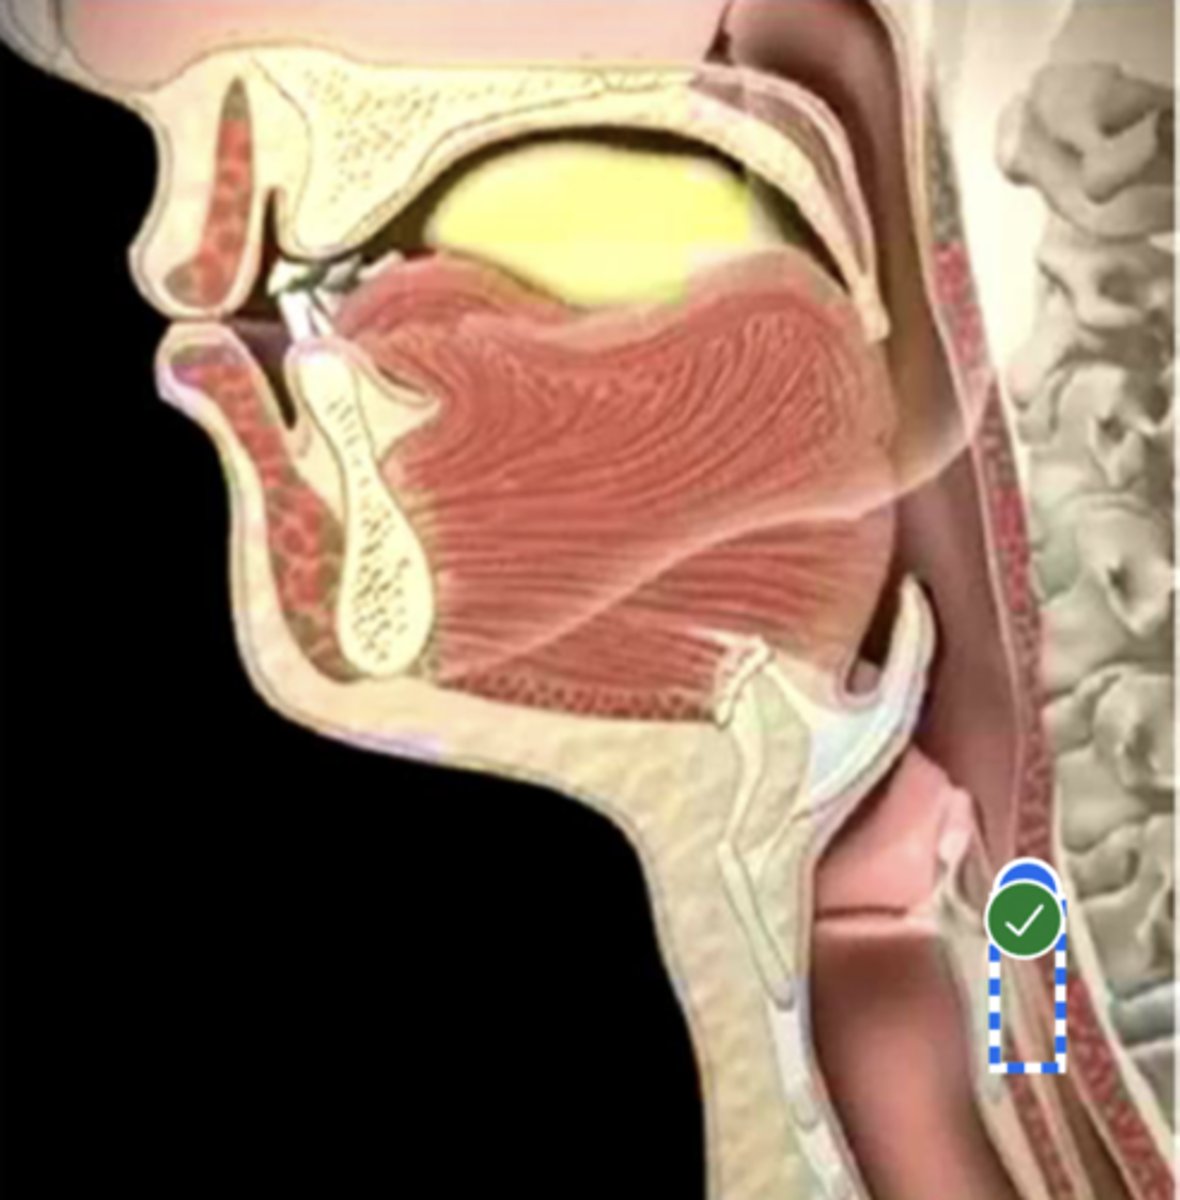

Label base of tongue (lateral view)

label anterior tongue (lateral view)

Label posterior/ back of tongue (lateral view)

Label Mandible (lateral view)

Label velum/ soft palate (lateral view)

Label hyoid bone (lateral view)

Label epiglottis (lateral view)

Label thyroid cartilage (lateral view)

Label posterior cricoid (lateral view)

Label trachea (lateral view)

Label upper esophageal sphincter (lateral view)

Label esophagus (lateral view)

Label posterior pharyngeal wall (lateral view)